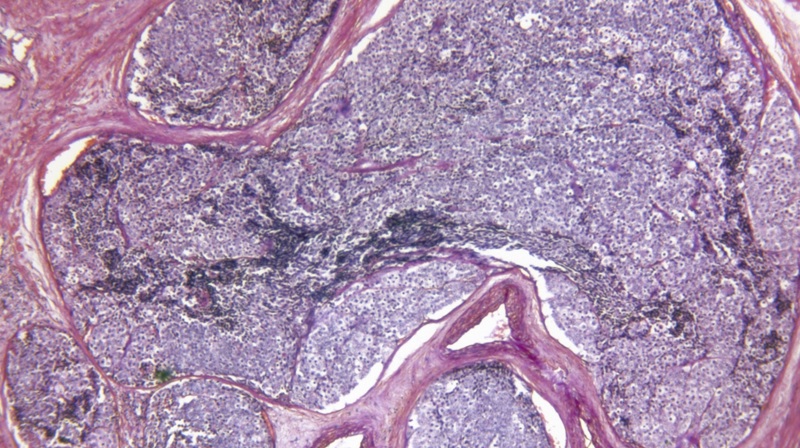

Cancer Slice

• The team used prostate cancer samples generously donated by men to see if KDM proteins are associated with the development of cancer.